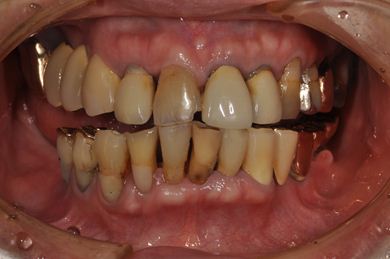

抜歯即日スピードインプラント治療+インプラント除去+セラミック治療

| 性別/年齢 | 女性 / 76歳 | ||||||||||||||||||||||||||||||||

| 主訴 | 20年前に入れたインプラントの周囲が腫れて気になっている。左下の一部治療後の歯が欠けている。 | ||||||||||||||||||||||||||||||||

| 治療内容 | インプラント5本(抜歯即日スピードインプラント)、ハイブリッドセラミック9本(セラミック用土台2本)、メタルボンドセラミック2本(メタルボンド用土台1本)、インプラント除去1本 | ||||||||||||||||||||||||||||||||